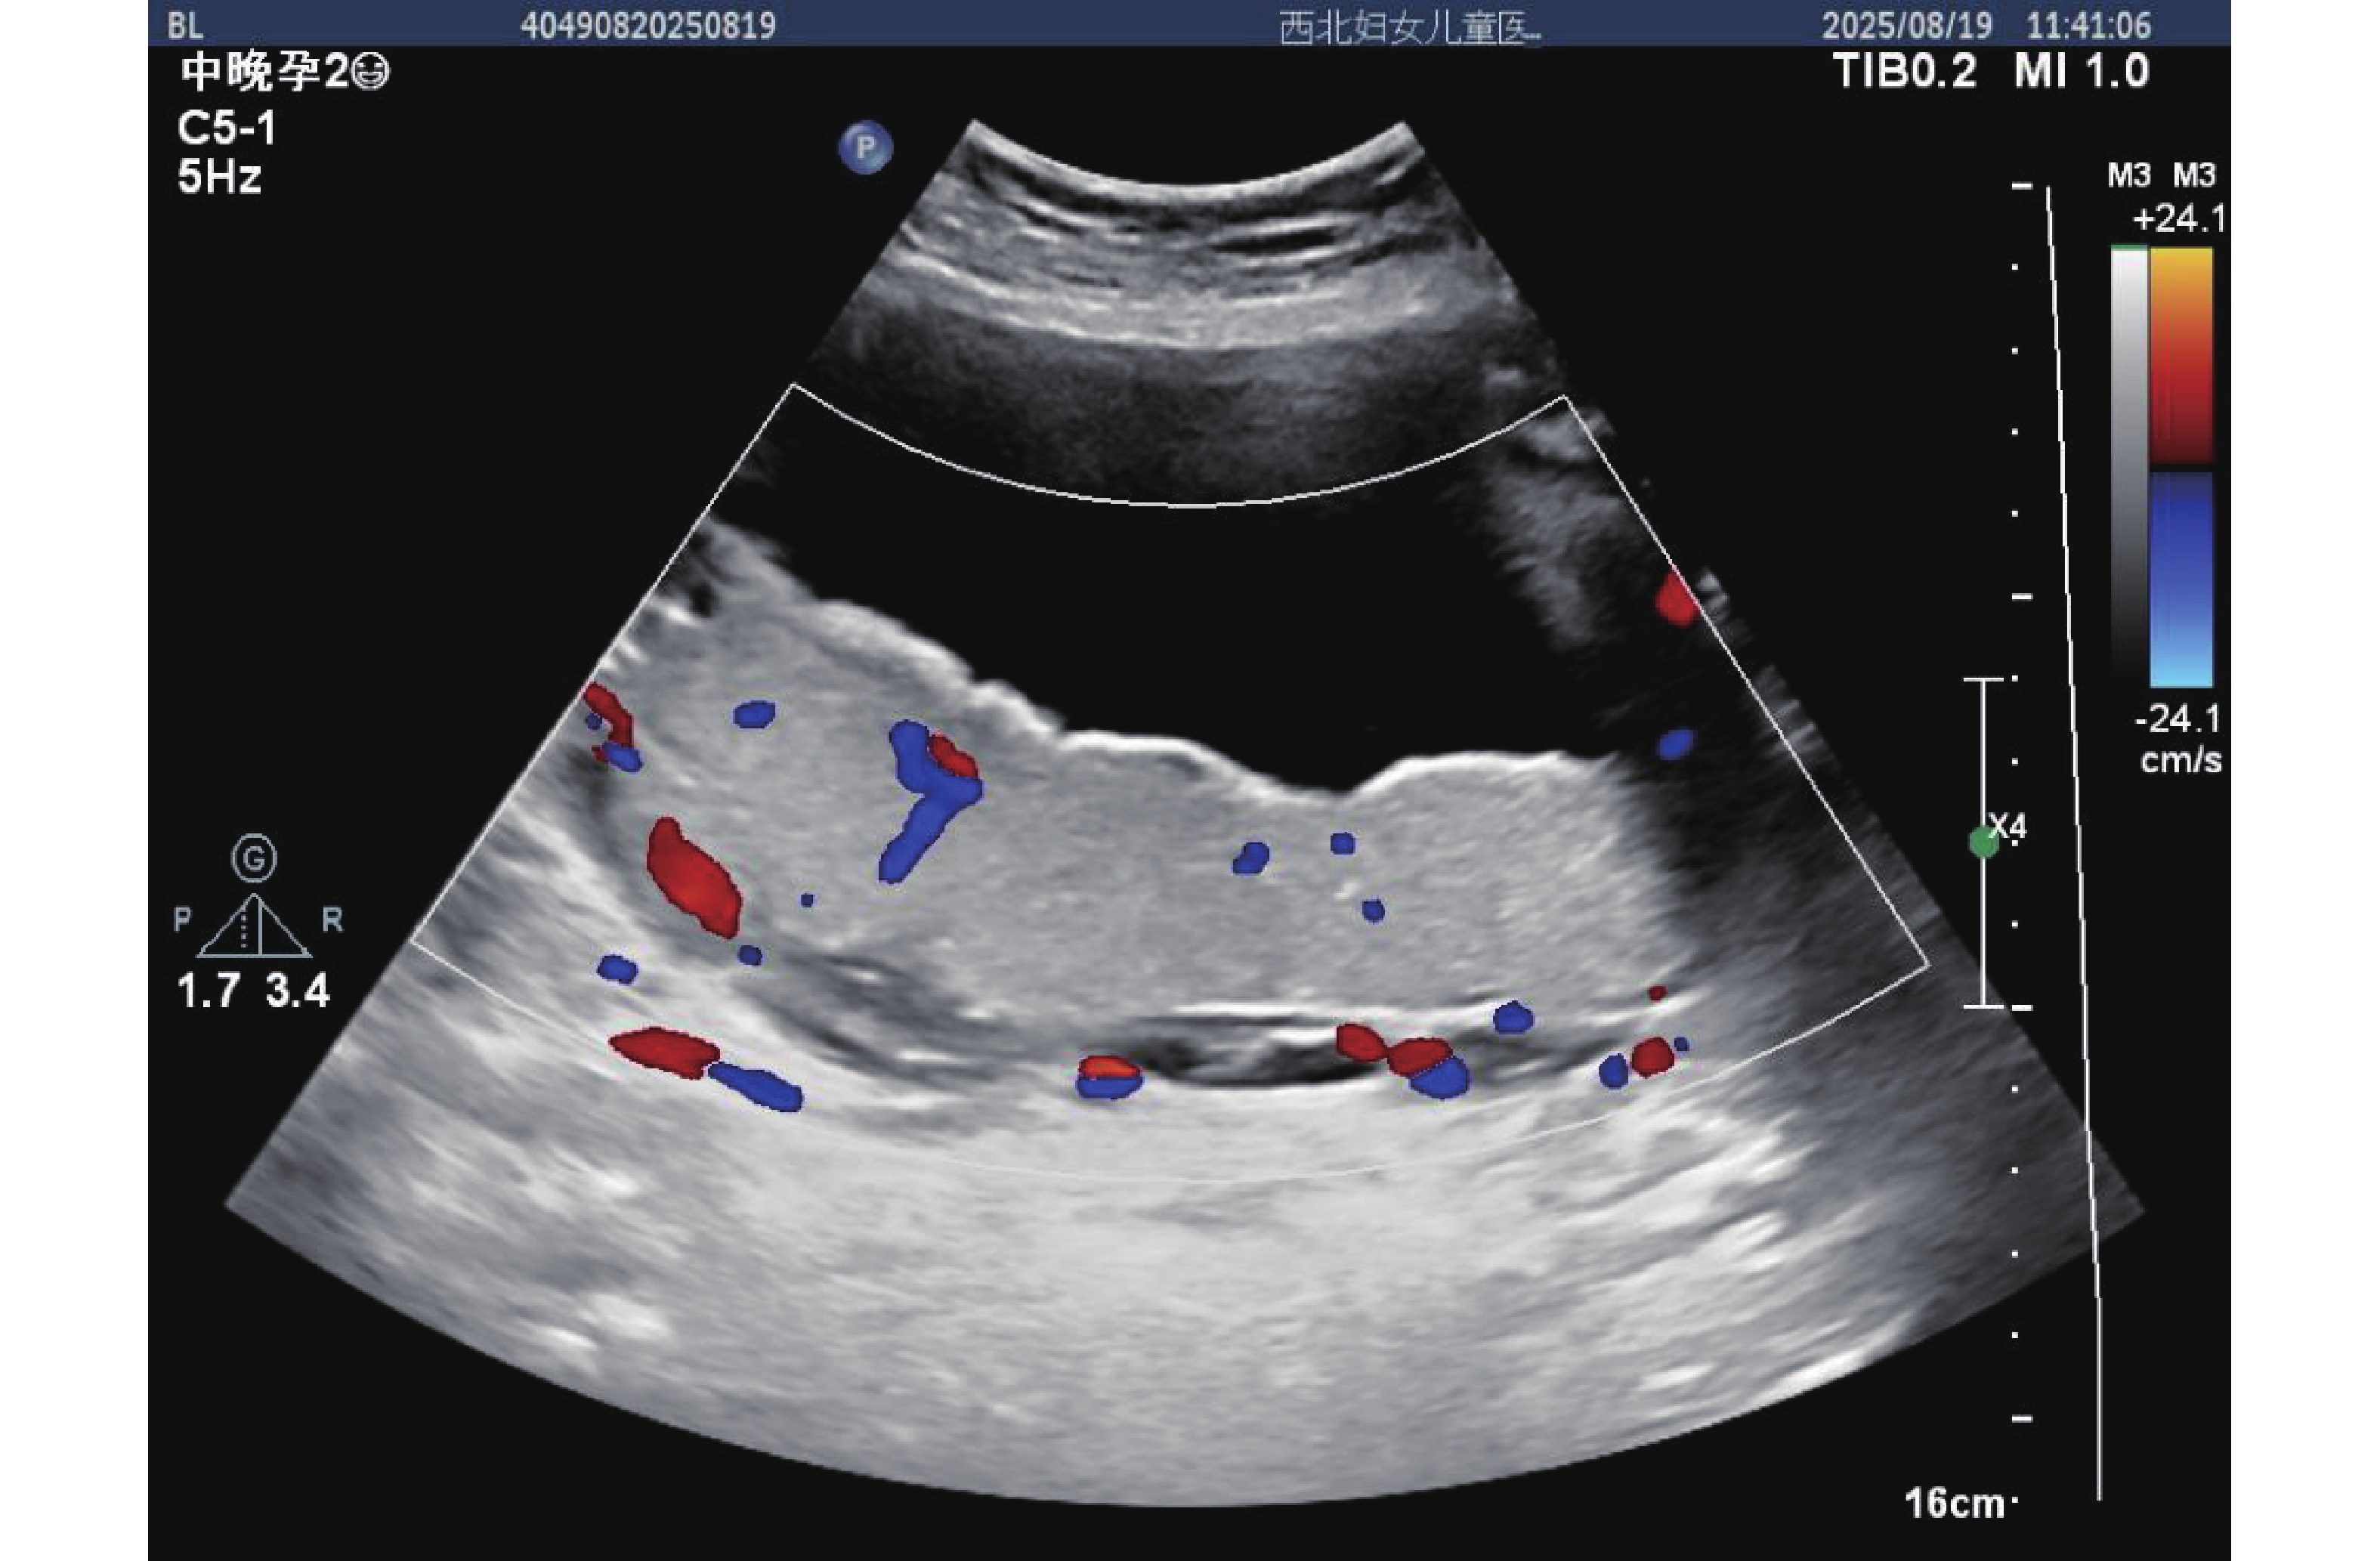

图  3  孕中期子痫前期孕妇胎盘超声影像

注:胎盘表面可见散在点状强回声(红色箭头指示),提示早期钙化倾向;彩色多普勒显示胎盘小叶间血流分支减少,血流信号强度减弱,反映胎盘血管床发育不良,灌注能力下降。

Figure  3.  Ultrasound image of the placenta in a pregnant woman with preeclampsia in the second trimester of pregnancy